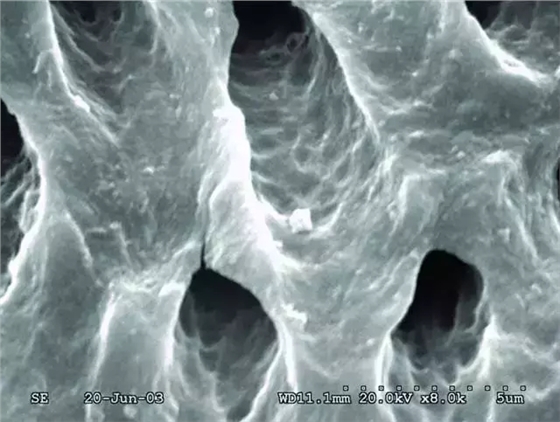

次氯酸鈉和EDTA沖洗預(yù)備后的根管壁。玷污層已去除,牙本質(zhì)小管打開(kāi)了,并且很潔凈。

高倍鏡下上圖中的牙本質(zhì)表面